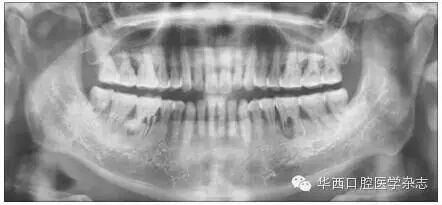

牙根折裂好发于下颌第一磨牙的近中根及上颌第一磨牙的近颊根、腭根,也可见于第二磨牙、前磨牙等(图12)。可以单发,也可对称性多发(图3)。可以是双侧的同名牙,也可以是同侧的上、下颌同名牙或相邻牙(图45)。

A:根尖片示36牙近中根根管细线样增宽;BCCBCT矢状位、轴位示近中根折裂;DECBCT矢状位、冠状位示同一患者26牙腭根横行折裂。

4 上、下颌第一磨牙牙根折裂

ABCBCT矢状位示3637牙近中根及2425牙根折裂;CD:轴位见1525牙根折裂(箭头示)。

5 上、下颌多发牙根折裂